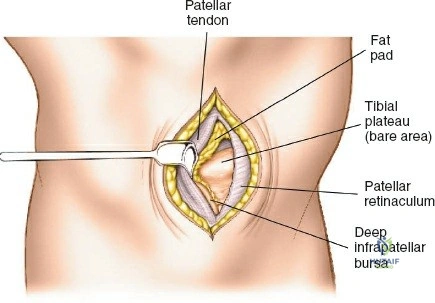

- Proximal Tibia: The preferred entry point for tibial nails lies in the proximal tibia, typically between the anterior tibial spine and the lateral edge of the patellar tendon. The infrapatellar fat pad (Hoffa's fat pad) must be navigated. Careful attention to the articular surface is paramount to avoid iatrogenic damage to the tibial plateau. The patellar tendon can be split or approached paratendinously, with long-term studies showing no significant difference in knee pain.

The incision should be adequate to allow clear access to the entry point and accommodate the targeting jig. The patellar tendon can be carefully split longitudinally or approached paramedially (medial or lateral to the tendon). - Entry Point Determination: The ideal entry point is crucial for proper nail alignment and preventing iatrogenic damage. It is typically located on the anterior cortex of the tibia, just medial to the lateral edge of the patellar tendon, distal to the articular surface of the tibial plateau.

- Fluoroscopic Guidance: Use an Awl or K-wire under AP and lateral fluoroscopy to confirm the entry point. The AP view should show the wire positioned to align with the central axis of the medullary canal. The lateral view should show the wire in line with the anterior cortex, avoiding a posterior entry which can damage the posterior cortex and lead to malalignment.

- Patellar Tendon Protection: Ensure the entry reamer or awl does not scrape the posterior aspect of the patella or damage the articular cartilage.